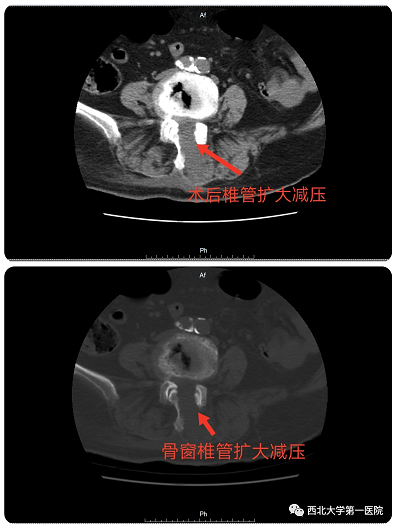

术后复查CT可见椎管彻底减压

经过充分的术前讨论及围手术期多学科讨论评估后,决定采用目前最新脊柱内镜技术:OSE(Open Spine Endoscope)单孔脊柱内镜技术,行腰4-5椎管狭窄单侧入路、双侧减压、脊神经根粘连松解术。手术切口约2cm,术中出血10ml左右,由于不破坏关节突关节,不影响脊柱稳定性。术后第二天患者佩戴腰带下地活动,症状明显缓解,效果非常满意。